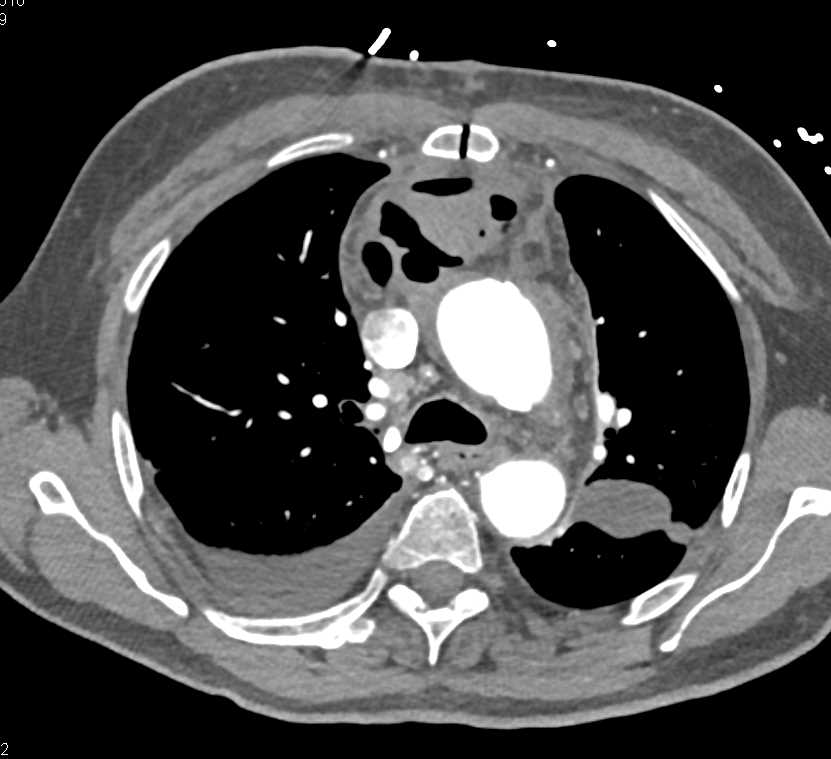

Cystic Changes Lung Fields and Infection